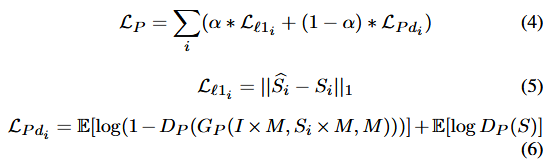

整个模型的损失函数由各模块的损失组成:

其中

L

C

L_C

LC为交叉熵损失,它在生成疾病数据时对生成器生成特定疾病类别的错误施加惩罚。

L

P

L_P

LP和

L

R

L_R

LR分别为PTM和RM的损失。

λ

∗

λ∗

λ∗表示每个损失的权重。

其中

L

l

1

L_{l1}

Ll1 是重构损失,计算生成结果与S之间的

l

1

l1

l1 距离,

L

P

d

i

L_{Pd_i}

LPdi 是判别器的对抗损失,

α

\alpha

α 是正则化参数。